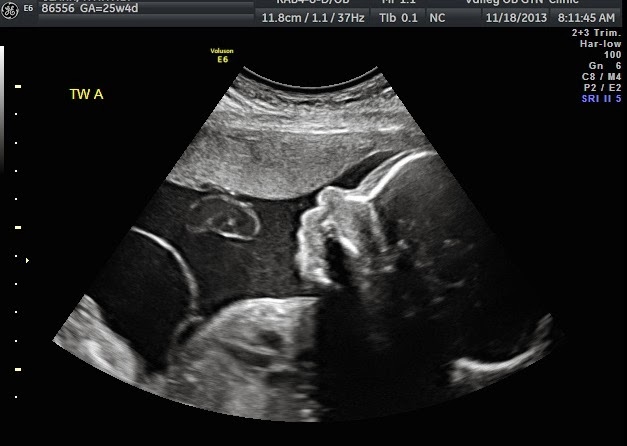

3D Pics (Because they are simultaneously adorable and creepy as hell!)

Baby A

her right hand is up by her forehead and her left arm is bent with her hand behind her neck

Baby A again

Baby B

she is chin to chest, you can see the depression in between her chest muscles

Ok, Baby B is literally cut in half in these pictures which is creepy as hell, but if you just focus on the top have she's soooo cute!

Baby B Disembodied head in her little sac...wow, creepy

Baby B one of my favorites, you can see her face chest and arm and part of her umbilical cord. She is facing the membrane between the two babies which is clearly seen in this picture. Just to the right of the membrane is Baby A her butt is at the bottom of the screen and then you can see her leg tucking around Baby B's head

My favorite! You can see Baby B smiling and Baby A's butt and leg!